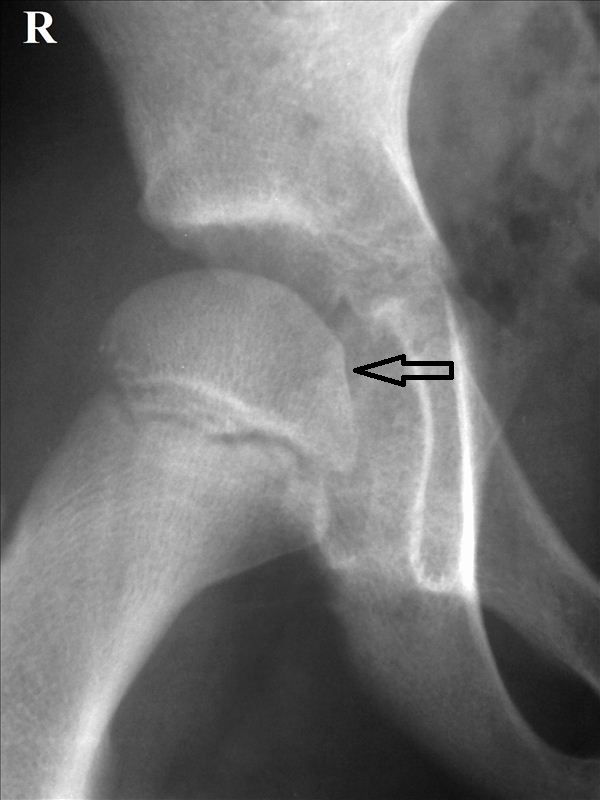

Диагностика ТБС рентгеном и асептический некроз: особенности лечения

Раздел: Снимки-откровения